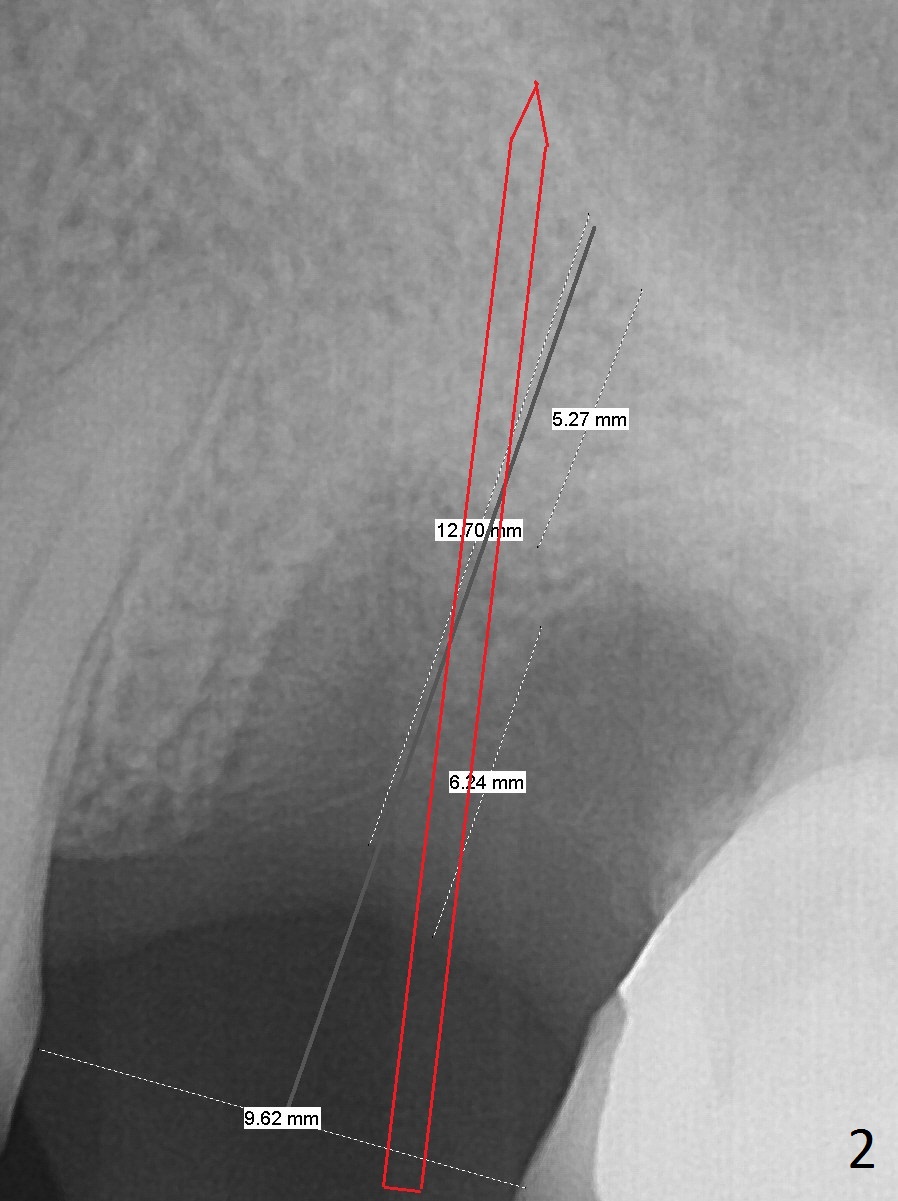

Low Density Post Extraction

A 44-year-old woman will return to clinic for #14 implant placement 2.5 months post extraction (Fig.1). The tooth used to have persistent fistula. The bone density appears to be low coronally. To compensate for the sloped sinus floor (arrowheads), start osteotomy as mesial as possible (Fig.2 red arrow) either with Magic Expander or Drill and place an implant as high as possible (Fig.3). If there is buccal plate defect, place the implant as palatal and deep as possible. Use Metronidazole routinely for sinus cases.